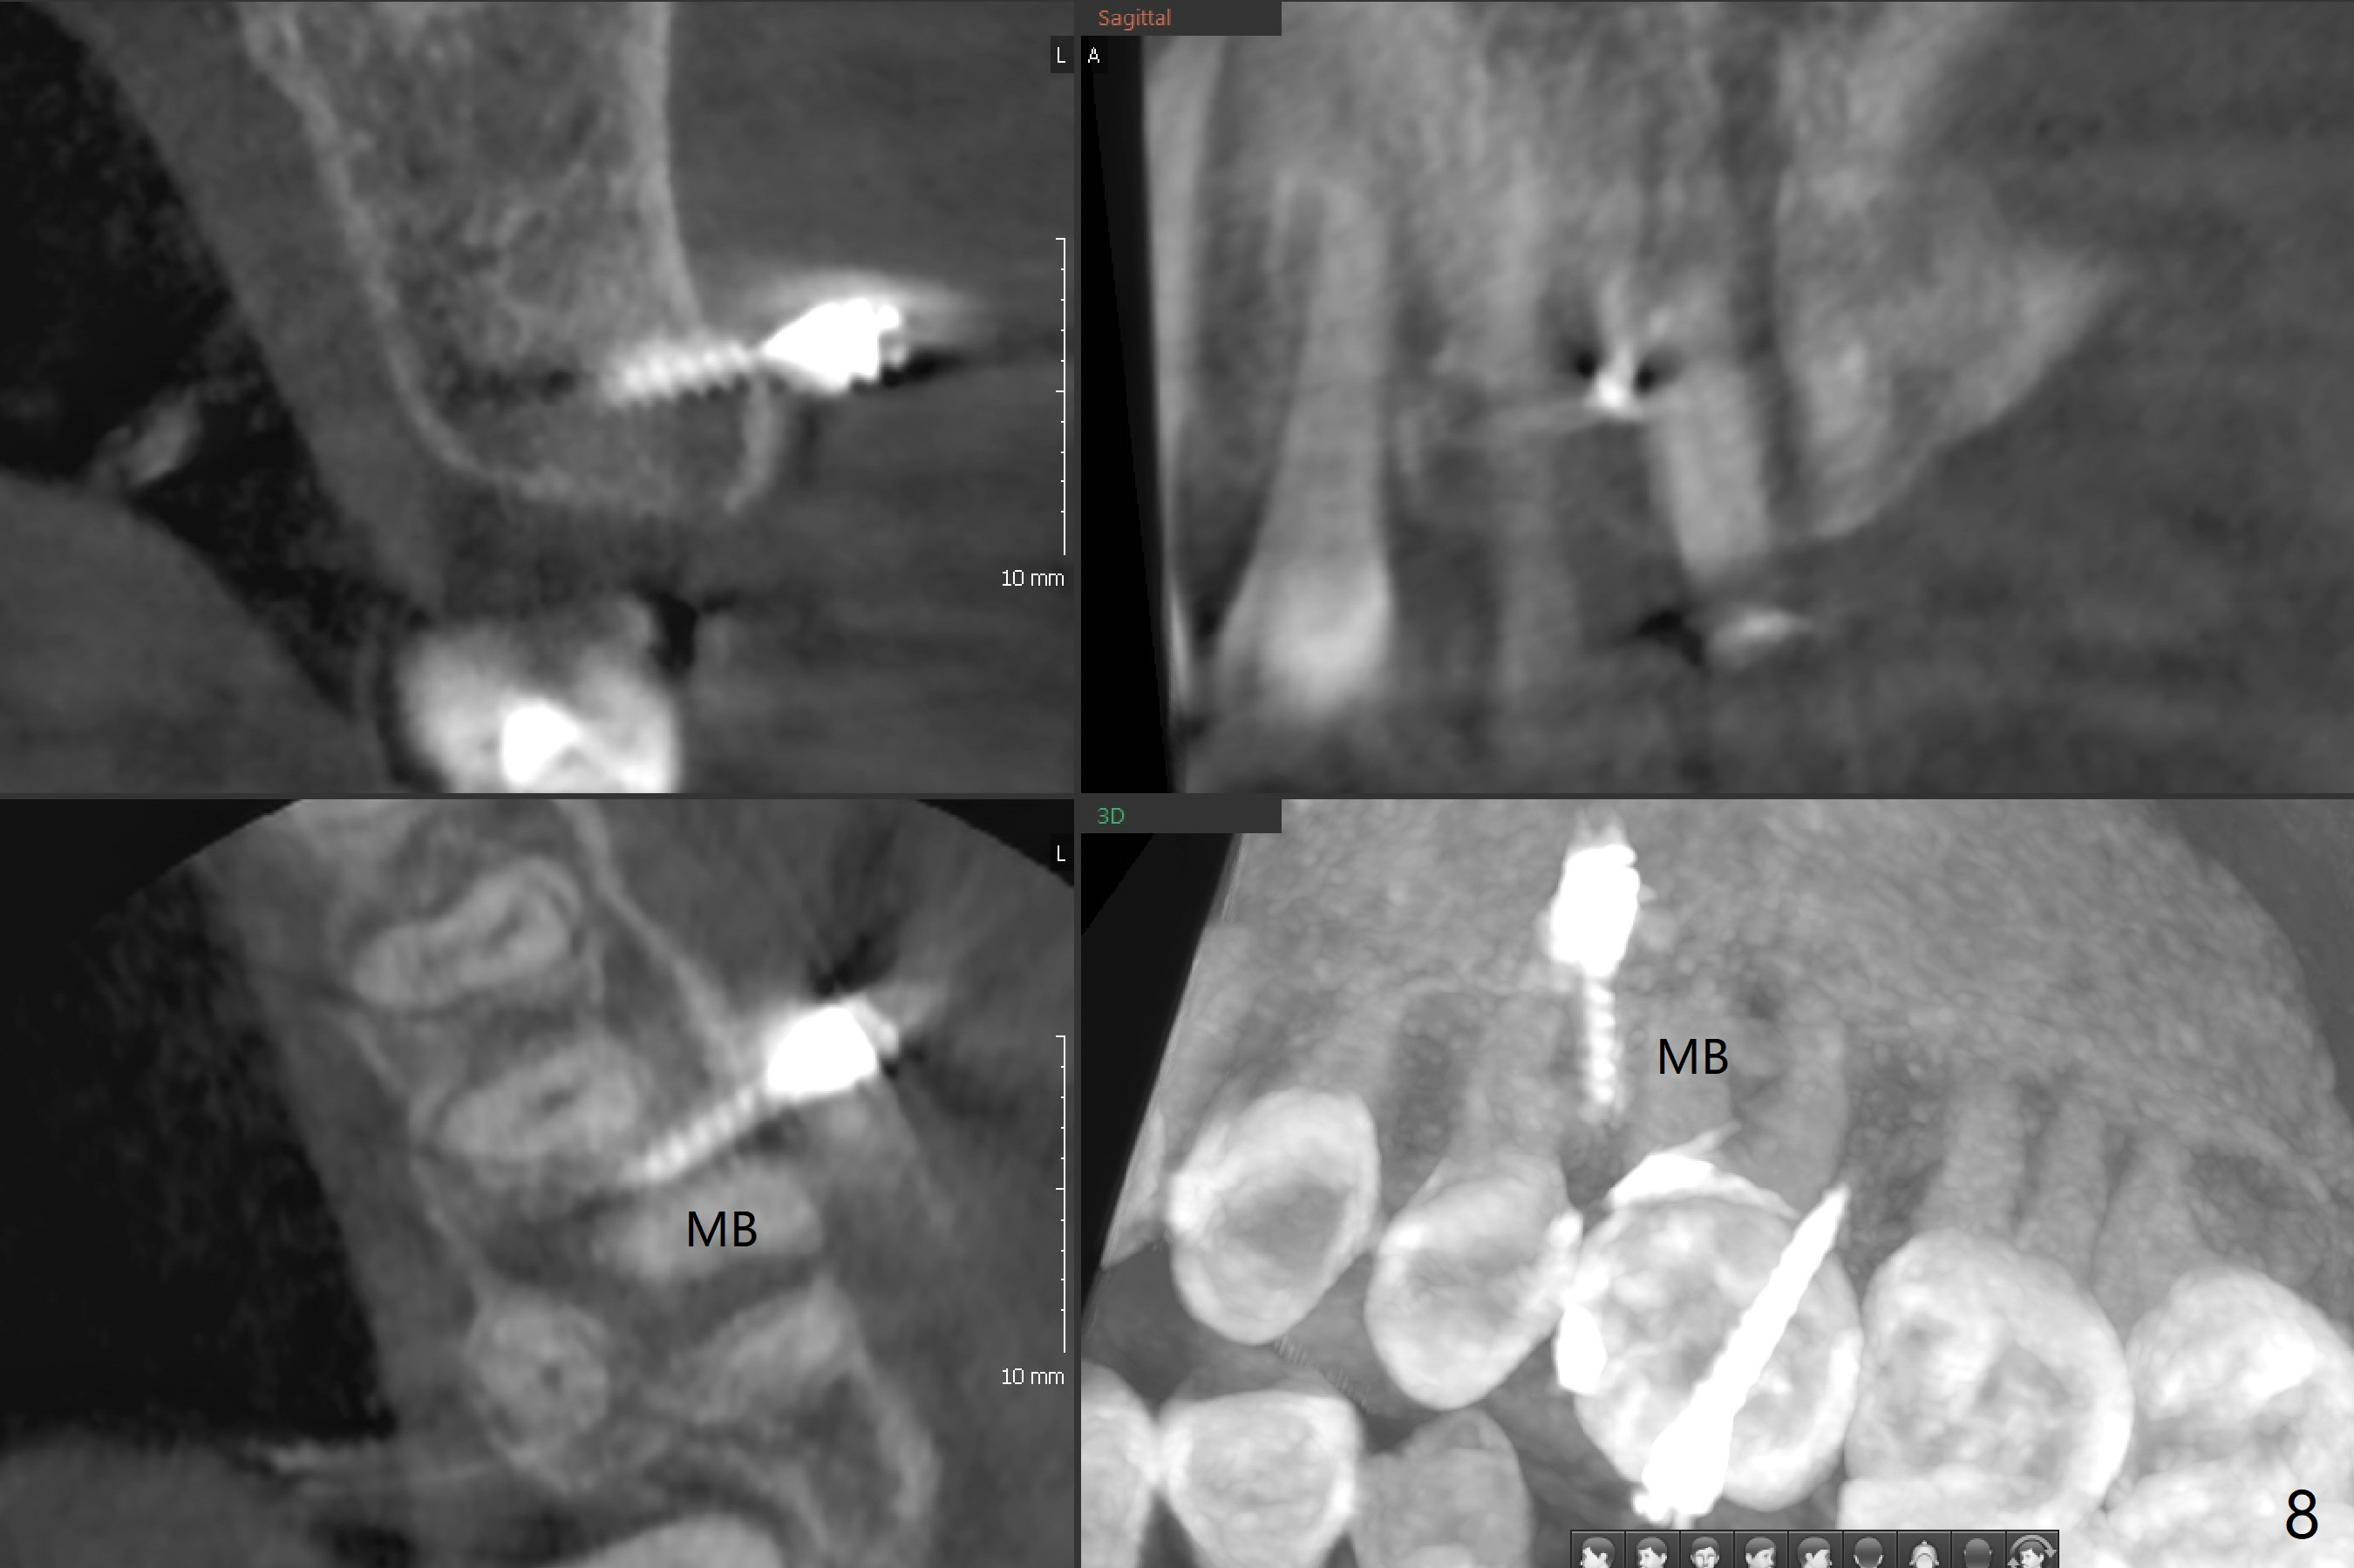

Fourteen days prior to implantation at #19 to replace a flipper (Fig.2), two minimplants are placed to intrude the supraerupted opposing tooth (#14, Fig.1). After use of minimal amount of local anesthetic (to keep proprioceptive in case root surface violation), the miniimplants are inserted ~ half of the length initially (Fig.3,4). The mesiobuccal (MB) one seems to be better positioned than the distopalatal (DP) one. When the implants are completely seated (Fig.5,6), three of PAs are taken, which suggests contact of the MB implant to the MB root of the tooth #14 (Fig.7 arrow). Immediately postop CT confirms approximation of MB and DP implants to the MB and P roots, respectively (Fig.8,9). The trajectory of these implants remain unchanged. Twelve days postop, the patient returns, uncomfortable with the palatal implant. After deep placement to bury the cuff (Fig.6) without local anesthesia (bone having no innervation), the patient feels better.